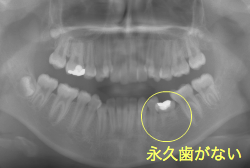

先天性欠如

先天性欠如とは生まれつき永久歯が部分的に欠如している状態をいいます。一般的に下顎前歯や小臼歯が欠如していることが多いです。

「左奥歯でものが噛めない」という主訴で来院したケースです。診断の結果、基本的には「叢生」という隙間が足りないと言うことが原因の凸凹症例でしたが、左下の乳歯が高校生になってもまだ残存している状態で、そのせいで噛み合わせが極端に悪くなっていました。

検査の結果、乳歯の下には後継ぎの永久歯が先天的に欠如していました。配列の凸凹が厳しく非抜歯で矯正することは難しく、仮に無理をして非抜歯治療をしても後々「後戻り」が懸念されることから、このような症例の場合は通常、上下顎左右第一小臼歯を抜歯させていただくのですが、左下は乳歯を抜歯して、第一小臼歯は残すことにしました。これで結果として、小臼歯部を上下左右で一つずつ減らしたのと同じ状況になります。治療後は歯並びが綺麗になっただけでなく、噛み合わせ的にも正しい状態が確立しています。

このように、先天的に永久歯が足りないという症例は最近増えています。親知らずはなくても特に問題になりませんが、その他の歯が足りないと言うのは審美的にも機能的にも重大な障害となります。しかし、矯正治療を正しく行えば、結果として歯がすべてあった場合と全く同じ仕上げにすることも可能です。